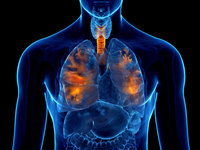

“근육통 주사 맞았다가, 갑자기 호흡곤란”… 사진 찍어보니 폐에 ‘이것’ 박혀 있어